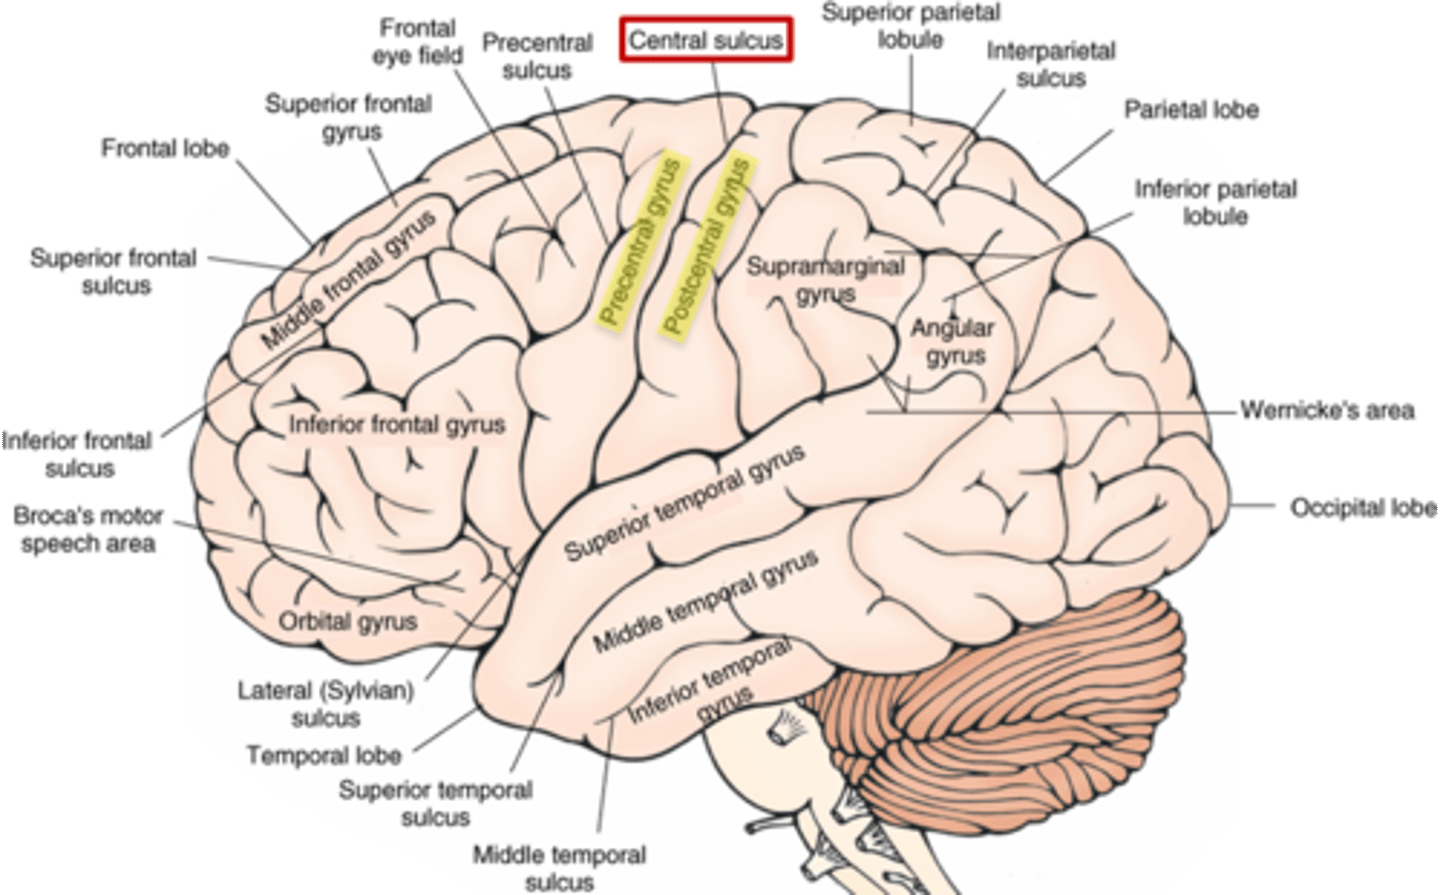

which sulcus separates the cerebral hemispheres?

longitudinal fissure

which sulcus divides the frontal lobe from the parietal lobe and divides the precentral and postcentral gyrus?

central sulcus

which sulcus divides the parietal lobe from the temporal lobe?

lateral (sylvian) sulcus/fissure

which sulcus separates the parietal lobe from the occipital lobe?

parieto-occipital sulcus

which gyrus is the primary motor complex?

precentral gyrus

which gyrus is the primary somatosensory complex?

postcentral gyrus